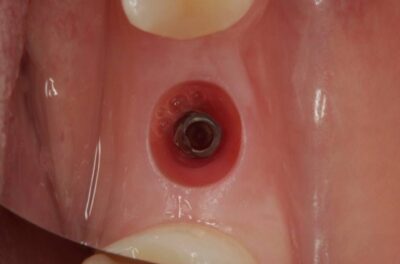

Специализация: терапия(эндодонтия), ортопедия, имплантология.